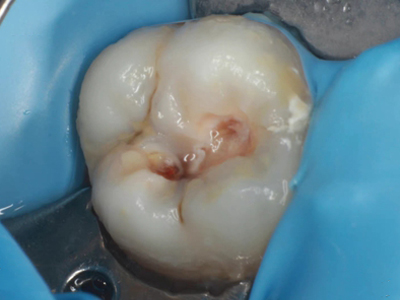

年轻恒牙龋指的是儿童萌出不久的第一恒磨牙龋病和上颌恒切牙龋病,其中第一恒磨牙龋病占年轻恒牙龋的90%,发病早,进展快,可表现为白垩色斑片、点隙窝沟墨浸状龋坏或龋洞。本病的发生和年轻恒牙的特点以及儿童饮食、口腔卫生等因素有关。

年轻恒牙龋好发于第一、二恒磨牙(牙合)面、邻面,上颌中切牙邻面,多为急性龋,龋坏进展快。平滑面的早期龋多为白垩色的斑片,点隙窝沟的早期龋多为浸墨状,表面粗糙。如果早期龋不及时治疗,可逐渐形成大而深的龋洞,易导致牙髓炎和根尖周炎。